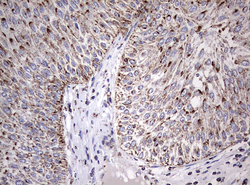

Supportive validation

- Submitted by

- OriGene (provider)

- Main image

- Experimental details

- Immunohistochemical staining of paraffin-embedded Carcinoma of Human bladder tissue using anti-ADAMTS1 mouse monoclonal antibody. (TA804503) Dilution: 1:150

- Validation comment

- IHC